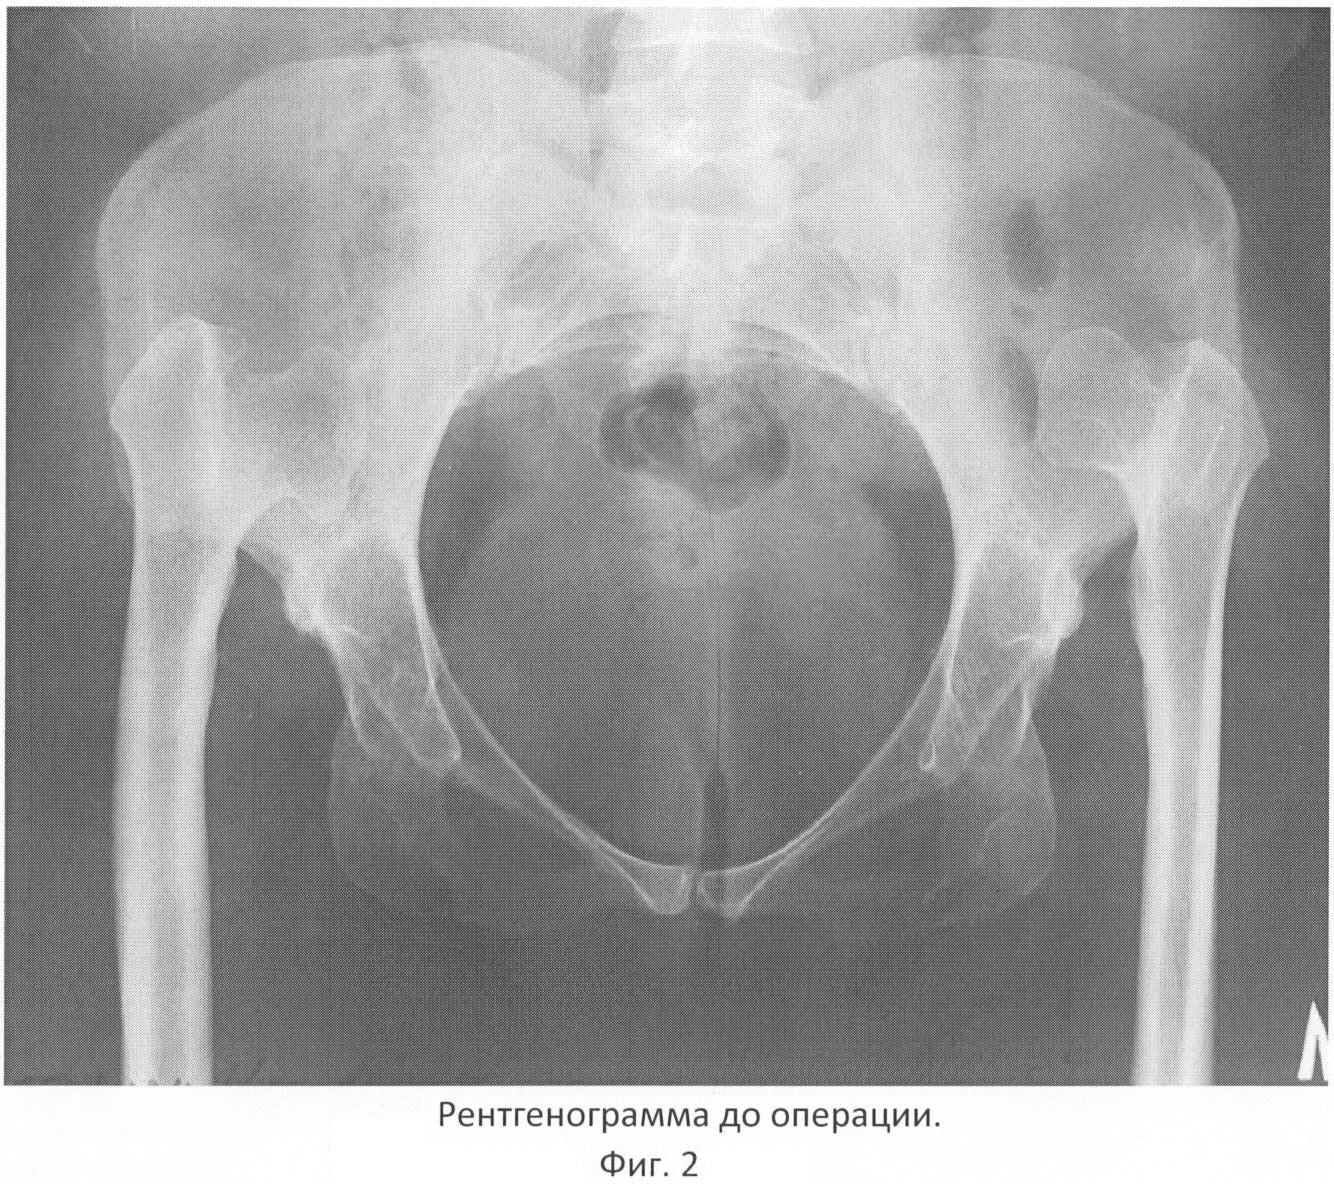

Больная И., 45 лет, в анамнезе – двусторонний врожденный вывих бедра, никакого лечения в детстве не проводилось. В последние несколько лет отметила изменение походки, появление боли в тазобедренных суставах в ночное время, усилилась боль в тазобедренных суставах, хромота. В последние 2 месяца наступило ухудшение состояния, связанное с резким усилением болевого синдрома, больная перестала ходить. При рентгенографии диагностирован двусторонний врожденный вывих бедер со значительным смещением головок бедренных костей кверху, дисплазией вертлужных впадин и бедренных костей. В течение месяца проводилось консервативное лечение в больнице – без эффекта. Поступила в ГВКГ им. акад. Н.Н.Бурденко для оперативного лечения. При поступлении – ходит без дополнительных средств опоры, с трудом переставляя ноги. Положительный симптом Тренделенбурга с обеих сторон. Отмечена гипермобильность тазобедренных суставов, резкая болезненность при движениях. На рентгенограммах: головки бедренных костей овальной формы, смещены кверху, образуя неоартроз с крыльями подвздошных костей, костномозговые каналы бедренных костей узкие, до 12 мм, недоразвитие истинных вертлужных впадин, диаметр их не более 36 мм, расстояние от головок бедренных костей до истинных вертлужных впадин 12 см (фиг.2).

На предоперационном планировании решено провести двухэтапное оперативное лечение – сначала низвести головки бедренных костей в аппарате Илизарова до уровня истинных вертлужных впадин, затем выполнить одноэтапное двустороннее эндопротезирование тазобедренных суставов.